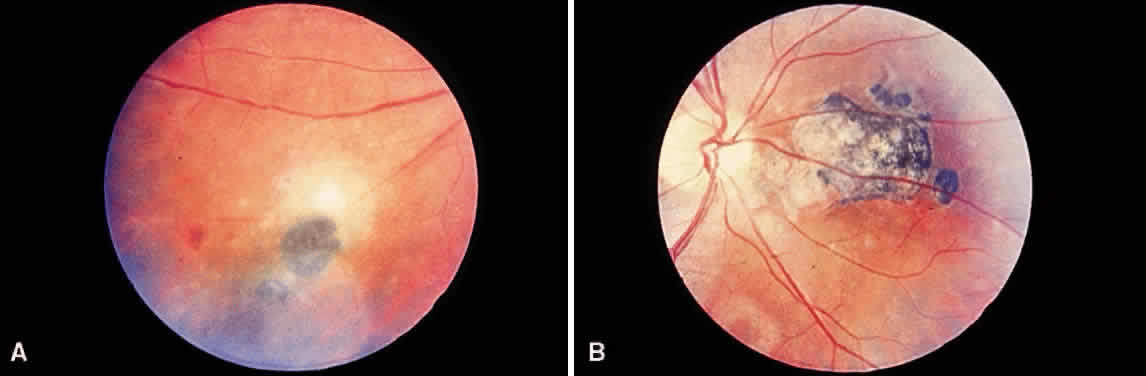

Bradyzoites are slowly metabolizing organisms found in cysts formed within the tissue of the infected host. The size of the Toxoplasma cyst varies, depending on the number of organisms that have multiplied within it. The cyst may reach more than 100 μm in diameter and may contain from 50 to 3000 organisms. The cyst wall is strongly argyrophilic and periodic acid-Schiff positive. It contains constituents that are derived from both the parasite and the host tissue. Constituent from the host tissue compose the outer part of the cyst, whereas those derived from the parasite are in the inner part of the cyst wall. Toxoplasmosis may be found in the inner layers of the retina after episodes of acute retinochoroiditis. The cyst may stay in the retinal tissue for years without showing any signs of invasiveness. Considering that the tissue cyst incorporates elements derived from the host into its outer wall, it is easily tolerated by the host, and no inflammatory reaction is seen around it (Fig. 2). It may remain for years in certain tissues, such as the eye or muscles, without provoking any inflammatory reactions. The bradyzoite inside the cyst derives its nutrition from the slow diffusion of substances through the cyst wall. The number of organisms increases within the cyst in the retina, and once the cyst wall breaks down by mechanical stretching, the bradyzoites escape, convert into tachyzoites, and invade contiguous cells. This process may lead to recurrence of retinitis. Certain immunologic mechanisms of the host may influence the organisms significantly. Immunosuppression coinciding with the rupture of the cyst and release of bradyzoites allows the organisms to become tachyzoites and proliferate in host tissue without restriction. The cyst of the Toxoplasma organism appears to be a defensive stage in its life cycle. The resistance of toxoplasmosis within chronically infected tissues of animals may lead to transmission of the disease by the ingestion of undercooked meat, including mutton, beef, pork, and chicken. Tissue cysts can develop within any organ and are commonly found in infected tissues of brain, eye, heart, skeletal muscles, and lymph nodes. Rupture of tissue cysts causes reactivation of the systemic toxoplasmosis in immune deficiency states, leading to dissemination of Toxoplasma organisms to other organs.